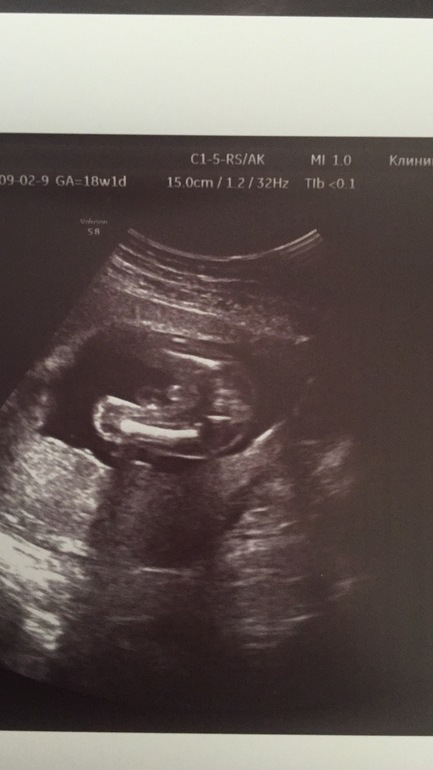

Чуточку постарше фото в 17 недель